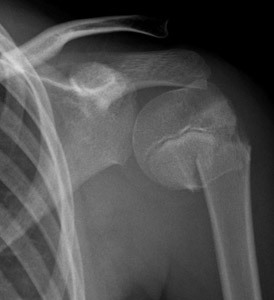

Acceptable alignment of a humeral shaft fracture

< 20° anterior angulation

< 30° varus/valgus angulation

< 3 cm shortening